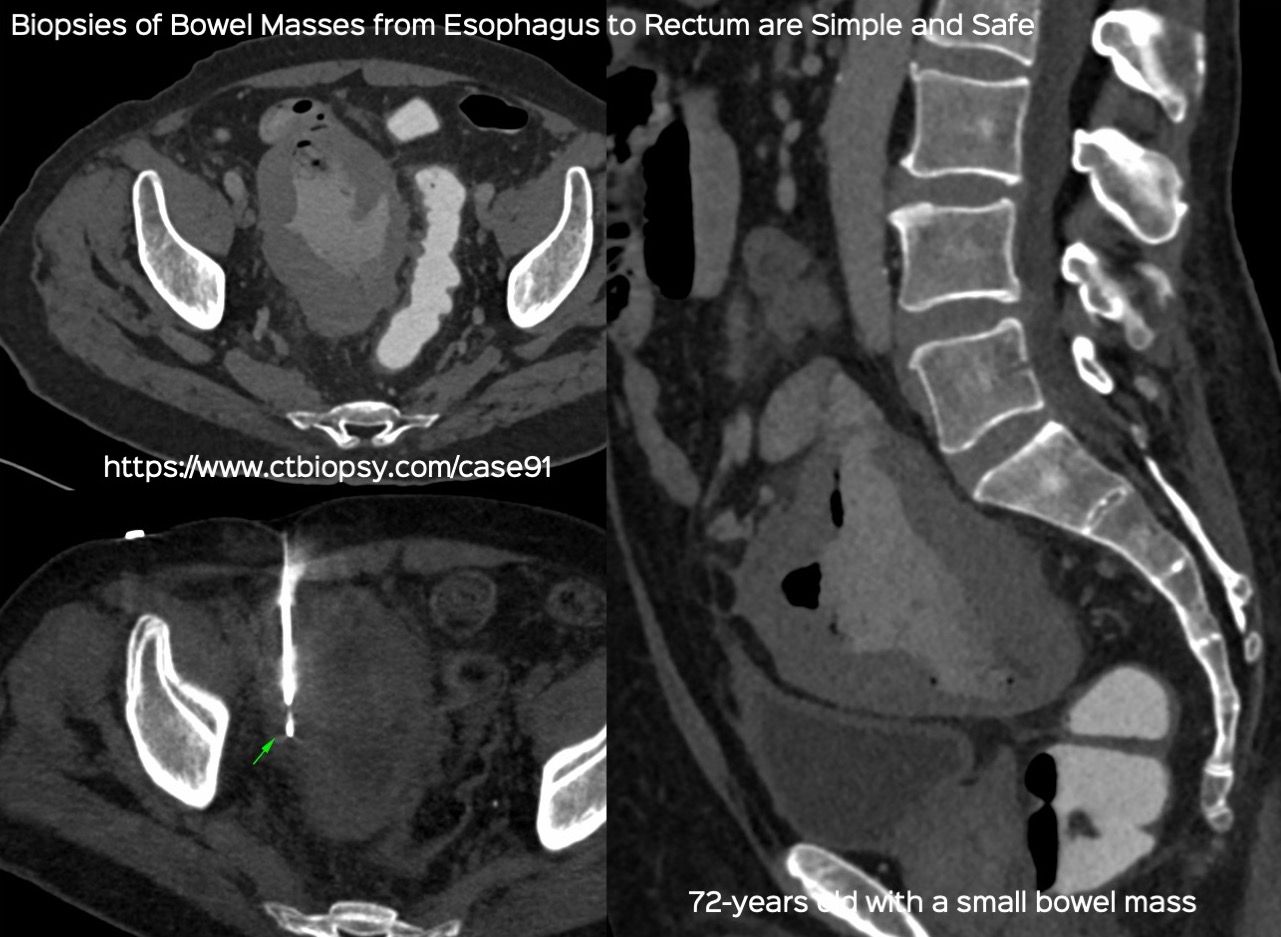

Case 91: Small Bowel Mass Biopsy